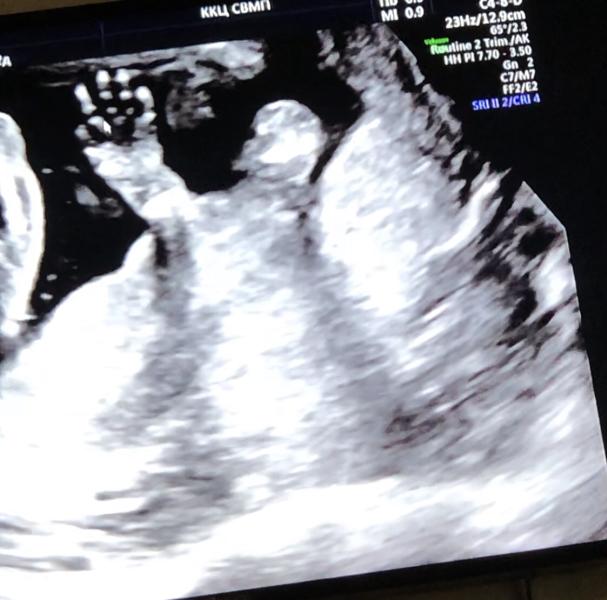

Ну что по всем таблицам и признакам у нас должна была быть девочка 👧🏻 по обновлению крови тоже девочка от мяса отвернуло с самого начала и сердцебиение было как у девочки , но наш папа с самого начала сказал что пацан и на узи был не поколебим , даже глазом не моргнул когда показали достоинство сына на весь экран ) Делали узи опять у Турсина показал все , рассказывал так мило , вот мордашка , вот пальчики ( ещё когда не добрались до низа говорит длинные такие пальчики наверно девочка ) а тут ниж...